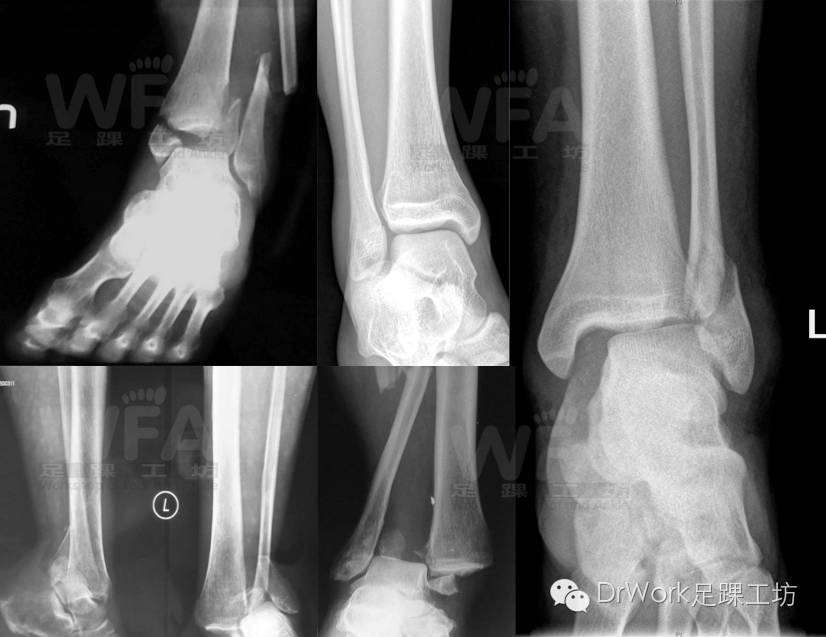

该患者正位片、踝穴位均正常

• TFCS:5mm

• TFO:10mm

• 胫距角:81o

• 内踝间隙:2mm

但CT显示相对于健侧下胫腓存在分离